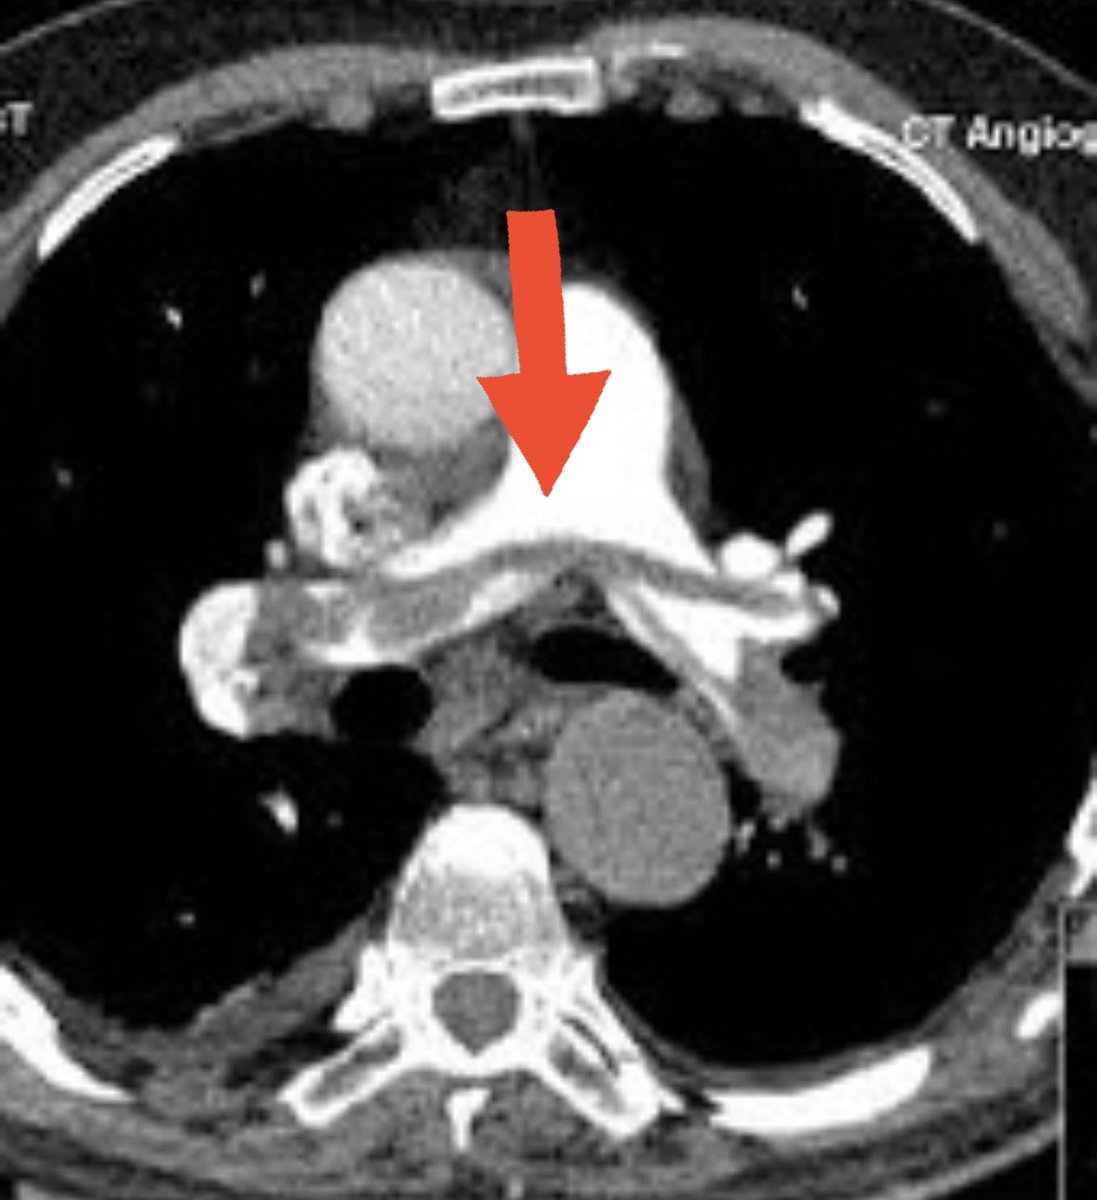

🚨 Thread: Radiology in Common Emergencies 🚨1/x #Medtwitter #radiology #Emergency potential #neetpg questions